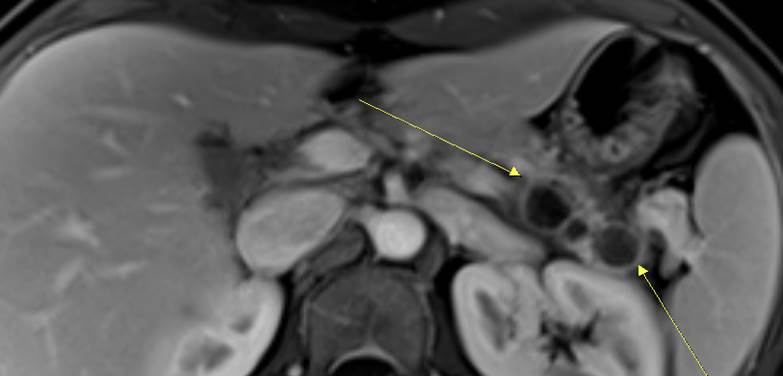

PancreasÀÇ multicystic lesionÀ¸·Î ³»¿øÇÏ¿© °á±¹ ¼ö¼úÀ» ¹ÞÀ¸½Å ºÐÀÔ´Ï´Ù.

ÃÖÁ¾ °á·ÐÀº pancreas neuroendocrine tumor¿´½À´Ï´Ù.